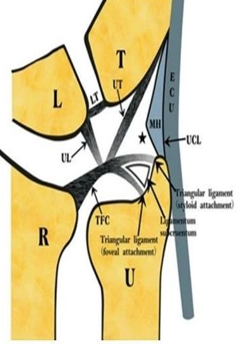

三角纤维软骨复合体(TFCC)是手腕最重要的纤维软骨-韧带复合结构,位于腕关节尺侧,分隔尺腕和远侧尺桡关节。常被称为是腕关节的“半月板”。

TFCC由以下韧带和纤维软骨组成:固有三角纤维软骨(TFC)、背侧桡尺韧带(DRUL)、掌侧尺韧带(PRUL)、尺三角韧带(UTL)、尺月韧带(ULL)、月三角韧带(LTL)、尺侧腕伸肌腱(ECU)鞘、尺侧副韧带(UCL)及半月板类似体(MH)。

半月板同系物是关节盘远侧增厚的尺侧副韧带纤维形成半月板类似体,与关节盘共同起于尺骨背侧靠近尺骨的边缘,有尸解证实其附着于豌豆骨。

TFCC主要具有以下3个功能:远端桡尺关节(DRUJ)的主要稳定结构;稳定尺侧的腕骨;将尺侧腕骨所受的压力转移至尺骨远端。